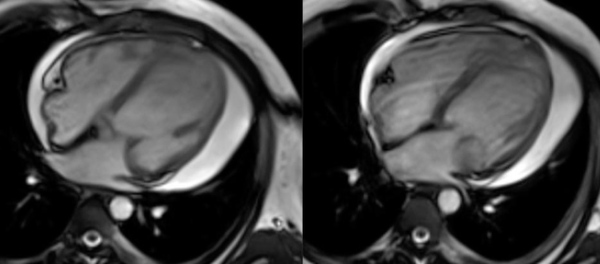

Myocarditis: CMR work-up.